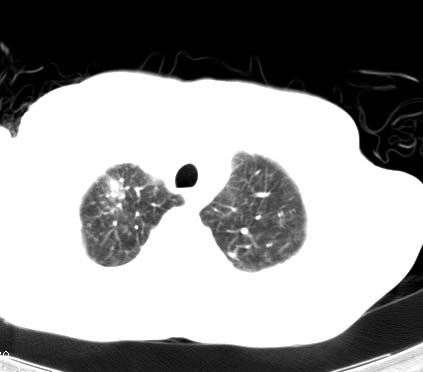

标题: CT14027:男性病人 71岁 咳嗽咳痰数周. [打印本页]

标题: CT14027:男性病人 71岁 咳嗽咳痰数周.

男性病人 71岁 咳嗽咳痰数周.诊断结核应该有保障吧!